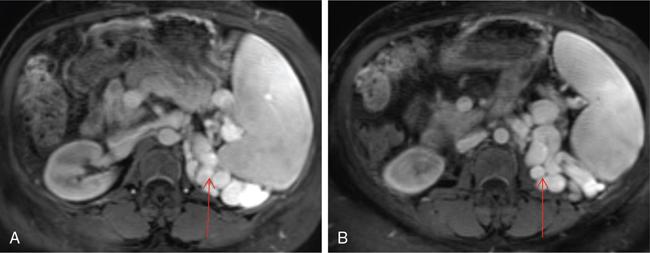

Shrinivas B. Desai, Ritu K. Kashikar, Aman Snehil, Ajay Jhaveri Cirrhosis is a late stage of irreversible scarring of the liver causing abnormality in liver structure and function. Multiple conditions and factors can cause repeated liver damage and scarring ultimately leading to cirrhosis. The most feared complication of liver cirrhosis is the development of hepatocellular carcinoma (HCC). Portal hypertension (PHT) is seen with a variety of conditions but cirrhosis happens to the most important cause. Imaging plays a vital role in noninvasive diagnosis and treatment planning of both cirrhosis and PHT. Liver imaging reporting and data system (LI-RADS) is a standardized reporting system assigning an observation risk of representing HCC. This chapter focuses on discussing aetiologies and imaging of PHT with a lucid review of L1-RADS 2018 version. The portal blood circulation is a unique circulatory circuit as it connects two capillary beds between the liver parenchyma at one end and the gastrointestinal tract and splenic parenchyma at the other end. The portal system ramifies in the liver and ultimately ends in the hepatic sinusoids from where the blood ultimately drains into the inferior vena cava (IVC). The portal vein (PV) originates from the capillary beds in the stomach, intestine and the spleen. The main PV is formed behind the neck of the pancreas by the confluence of the superior mesenteric vein (SMV) and splenic vein. It continues to the porta hepatis where it bifurcates into the left and right branches as it carries nutrient rich but oxygen poor blood to the liver (Fig. 9.9.1). The PV makes up for 75%–80% of the liver’s blood supply while the hepatic artery which arises from the celiac trunk makes up for the remaining 25%. A pathological increase in the portal venous pressure is referred to as PHT. PHT is most often a sequel of chronic parenchymal liver disease and leads to major life-threatening complications due to bleeding from the collateral circulation (most commonly oesophageal varices). Direct measurement of portal pressure (PP) is invasive and often not feasible in most patients and thus imaging plays an important role in the diagnosis of PHT and its complications. The normal portal venous pressure ranges between 5 and 10 mmHg, which is the equivalent of 7–14 cm H2O. The normal hepatic venous pressure gradient (HVPG) is the pressure gradient between the PV and the IVC, is typically 1–5 mmHg. Presence of PHT is indicated by a wedged hepatic venous pressure of more than 5 mmHg. Other definitions include a splenic pressure of more than 15 mmHg or an intraoperative PP of greater than 30 cm H2O. The complications of PHT are seen when HVPG is greater than 10 mmHg and hence this value defines clinically significant PHT. Variceal bleeding is seen with a pressure greater than 12 mmHg. In ideal conditions, the portal circuit is a high flow, low resistance circuit as it has to allow substantial flow rates of 700–1000 mL/min to the hepatic parenchyma from the gastrointestinal tract. Anatomical changes in the organization of the hepatic lobule can result in rise in the portal resistance. These can occur in the form of collagen deposition in the space of Disse, fibrotic scars formed due to regenerative nodule (RN) formation, loss of normal elasticity of the endothelium and distal venous thrombosis. Changes in splanchnic haemodynamics due to factors that increase splanchnic blood flow and increase in intrahepatic vascular resistance due to transformation of stellate cells into myofibroblasts also contribute to the increase in PP gradient. In Western countries, alcoholic cirrhosis and viral cirrhosis are the leading causes of PHT and oesophageal varices. The viral causes form majority of cases leading to cirrhosis and PHT in the Far East and Middle Eastern countries while Schistosomiasis remains an important cause in the African countries. Worldwide, nonalcoholic steatohepatitis (NASH) and hepatitis C are the emerging causes of chronic liver disease (CLD) and PHT. PHT can be classified as cirrhotic and noncirrhotic depending on whether it is associated with cirrhosis or not. This distinction is important as noncirrhotic causes like PV thrombosis are at high risk of development of bleeding but tend to have a better chance of surviving a variceal bleed than a patient with decompensated alcoholic cirrhosis due to preserved hepatic synthetic functions in the former. PHT can also be classified on the basis of the location of the pathology into prehepatic, hepatic and posthepatic causes. Hepatic causes can further be divided into presinusoidal, sinusoidal and postsinusoidal. The causes of portal hypertension have been denoted in Table 9.9.1. The direct measurement of the PP by measuring the HVPG is invasive, expensive not readily available in all patients. Thus, imaging plays an important role in the diagnosis of PHT. Various modalities are used for the imaging diagnosis of PHT. Ultrasonography (USG) and Doppler evaluation have the advantage of being inexpensive, readily available and bedside modality (Table 9.9.2). The role of ultrasound and Doppler in imaging of PHT is to: Grey scale imaging is useful in evaluating the splenoportal anatomy. The evaluation should begin with the liver morphology. Signs of cirrhosis like nodularity of the liver surface with relative atrophy of the right lobe and prominence of the left lobe and caudate should be looked for. Hepatic echotexture appears coarse and more echogenic (Table 9.9.3). Increase in portal venous diameter is a sign of PHT (Fig. 9.9.2). Portal venous diameter of more than 13 or 15 mm has low sensitivity for diagnosing PHT of only 40%–12.5%, respectively. Absolute measurement of the portal diameter as a sign of PHT is also fallacious as in presence of collateral circulation or hepatofugal flow; there may actually be a decrease in the PV diameter. Therefore, a more accurate sign is respiratory variation of PV diameter. An increase in PV diameter of less than 20% with deep inspiration has been reported to indicate PHT with a sensitivity of 80% and specificity of 100%. This has been reported to be an accurate indicator of cirrhosis. Hepatic vein straightness, uniformity of vein wall echogenicity and visualization of at least 1 cm segment of the hepatic vein are the parameters used for evaluation. Splenomegaly is defined as bipolar splenic diameter of greater than 12 cm or largest splenic cross-sectional area passing through the hilum of greater than 45 cm2, and occurs secondary to PHT (Fig. 9.9.3). A total of 65%–80% patients with cirrhosis have splenomegaly on ultrasound. Patients with cirrhosis due to viral hepatitis and primary biliary cirrhosis show splenomegaly more frequently than those with alcoholic cirrhosis. This is an accurate sign of PHT. USG is extremely sensitive with respect to detecting subclinical ascites. Perihepatic space is the most usual site of visualization of minimal ascites. In normal subjects, this ratio is approximately 0.07 and a value above 0.1 suggests the diagnosis of PHT with a 95% sensitivity and specificity. The normal spectral waveform of the hepatic artery is a low resistance flow pattern with forward flow in diastole and a resistivity index in the range of 0.5–0.7. In PHT, the resistivity index of the hepatic artery increases with high resistance flow pattern due to increased peripheral vascular resistance. Resistance index (RI) > 0.78 in the intrahepatic branches of the hepatic artery has been reported to have a sensitivity of 50% and a specificity of 100% for the detection of PHT (Fig. 9.9.11). Pulsatility index (PI) > 1.05 suggests severe PHT with a sensitivity of 86% and specificity of 88% (Fig. 9.9.11). Patency of hepatic veins should be evaluated to rule out Budd–Chiari syndrome as a cause of PHT. The normal hepatic venous waveform (HVW) reflects right atrial activity and this results in a triphasic waveform with one positive and two negative waves. In PHT, this waveform becomes monophasic or biphasic. A monophasic HVW has a sensitivity and specificity of 74% and 95%, respectively, in the diagnosis of severe PHT (Fig. 9.9.12). Dilatation of the splanchnic veins – the SMV and the splenic vein – more than 11 mm are suggestive of PHT with a sensitivity and specificity of 72% and 100%, respectively. A reduction in the respiratory variation of the splenic vein and SMV to less than 40% had a sensitivity and specificity of 79.7% and 100%, respectively, for the diagnosis of PHT (Fig. 9.9.13). The splenic artery reveals an increase in the resistivity index and an RI of >0.63 and a PI of >1 have a sensitivity and specificity of 84.6% and 70.4% for the diagnosis of PHT. Presence of portosystemic collaterals like patent paraumbilical vein, dilated left gastric and short gastric veins are 100% specific sign for PHT (Figs. 9.9.14–9.9.16). Recanalization of the paraumbilical vein, known as the Cruveilhier–Baumgarten syndrome is observed in 43% of patients with PHT, and this is the easiest collateral to assess during the US examination. Various portosystemic collaterals that occur in PHT have been discussed in details in subsection on CT findings in PHT. No Doppler parameter is considered reliable enough to measure PP with sufficient accuracy for use in clinical practice. Oesophageal varices are often present in patients with portosystemic collaterals. Appearance or increase in number of collaterals along with splenomegaly has a high association with variceal formation and growth. USG helps in diagnosis of prehepatic causes like portal stenosis or thrombosis by demonstrating the patency and morphology of the splenoportal system. Arteriovenous fistulae and tumours causing vascular thrombosis as aetiology can be readily detected. USG helps in diagnosis of features of cirrhosis and thus helps differentiate noncirrhotic causes of PHT. USG allows diagnosis of fatty liver disease, which is an emerging cause of cirrhosis. Among the posthepatic causes, USG aids in establishing the diagnosis of Budd–Chiari syndrome by demonstrating the patency and morphology of the IVC and hepatic veins. Owing to the inability of CT to detect flow direction, portal flow rates or pressure gradients, CT is not the primary modality in diagnosis of PHT. Similar to USG dilatation of portosystemic system is a feature of PHT (Fig. 9.9.17). Changes in cirrhosis if present can be seen in the form of surface nodularity, nodules and fibrous septae. CT plays an important role in diagnosis of portal venous thrombosis and evaluating its extent. An acute thrombus is seen as a hypodense filling defect in the vessel causing distension of the venous lumen. Surrounding fat stranding can be seen. A chronic thrombus appears as an eccentric filling defect usually along the wall and is often associated with decrease in vessel diameter. Calcification may be seen in chronic thrombi. Multidetector computed tomography (MDCT) is a useful tool to evaluate portosystemic collateral circulation and recognize complications of PHT. 3D angiography can help understand portal venous and complex variceal anatomy and plan treatment. The various portosystemic collaterals are discussed below. They can be classified into those draining into superior vena cava (SVC) and those draining into the IVC. Magnetic resonance imaging (MRI) is a noninvasive modality used in the evaluation of PHT without the use of ionising radiation. It provides evaluation of parenchymal abnormalities, collaterals and characterization of tumours (Fig. 9.9.28). Spin echo sequences allow characterization of liver masses and liver parenchyma. Loss of flow void allows for detection of thrombosis. Time-of-flight (TOF) angiography is useful in assessing the portal venous system and allows for successful detection of PV thrombosis. The disadvantages of TOF are motion artefacts caused by breathing, long acquisition times and incomplete coverage of the portal venous system. Novel imaging techniques include phase contrast, T1 mapping and magnetic resonance elastography (MRE). The advantage of phase contrast over TOF imaging is that phase contrast imaging acquires information regarding the flow direction in addition to the information regarding the flow velocity. On-phase contrast images signal within vessel is hyperintense when flow is cranial and hypointense when flow is caudal. Look-Locker imaging technique using gradient echo (GRE) MRI sequences with inversion recovery pulse is used to quantify fibrosis by measuring precontrast T1 relaxation times. Interventions in PHT can be aimed at diagnosis or more commonly at management of complications of PHT. HVPG measurement, which is the gold standard for the diagnosis of PHT, can be achieved through cannulation of the PV. Transjugular hepatic biopsy is another diagnostic invasive technique that also allows indirect measurement of PP. Disadvantages include deterioration of hepatic function caused by diversion of portal venous blood flow and shunt dysfunction. TIPSS is contraindicated in patients with congestive heart failure, severe pulmonary hypertension, severe tricuspid regurgitation and hepatic failure. In this technique, a catheter is advanced from the femoral vein into the outlet of the gastrorenal, usually in the region of the left renal vein. The shunt is then occluded with a balloon and sclerosant is injected retrograde to occlude the gastric varices. Histological development of RNs surrounded by fibrous septae in response to chronic liver injury, progressing PHT and end-stage liver disease is termed as cirrhosis. Although initially considered an end-stage phenomenon in CLD, recent evidence suggests that the histological fibrosis can be reversible in early stages with the initiation of specific therapies, for example, in viral cirrhosis with the initiation of antiviral therapy. The one-year mortality rate in cirrhosis varies widely from 1% to 57% depending on the occurrence of complications. Cirrhosis can have a wide variety of causes ranging from congenital to acquired and infectious to noninfectious. It is also a major aetiologic risk factor for the development of HCC. Imaging plays an important role in aetiologic diagnosis of this diverse entity as well as in the diagnosis and management of its complication and surveillance for oncological transformation.

Role of MRI and newer techniques